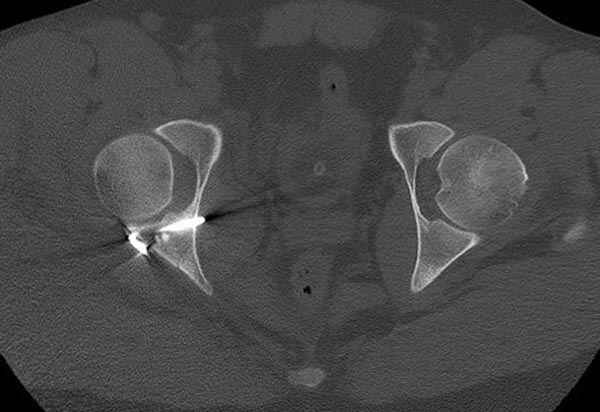

11:50 больной в послеоперационной, рентгенограмма N7, компьютерная томограмма в тот же день N8-10

7:30 начало операции, больной на спине, попытка репозиции после анестезии N3, укладка больного на боку, доступ Kocher- Langenbeck, состояние седалищнего нерва около 2.5см кровоподтек, через joistick головка бедра приподнята, освобовождение сустава, фрагмент заднего края более 3х4 см репонирован на свое место. После промывания

сустава, репозиция вывиха (N4), фиксация фрагмента 2.7(4) мм шурупами и допольнительно реконструктивной пластиной на 8 дырок, фиксация 3.5мм шурупами проксимально и дистально.